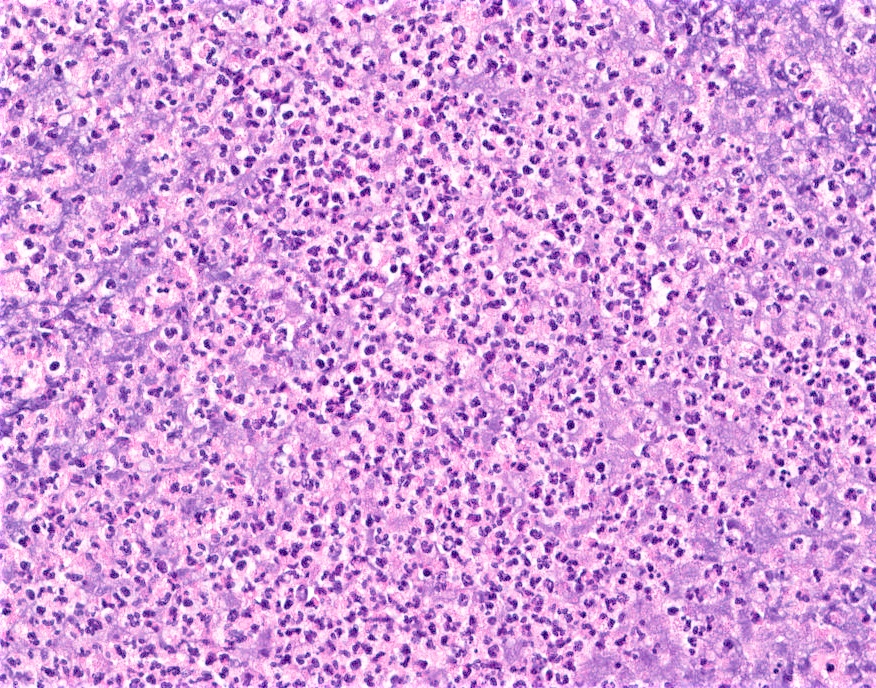

Microscopic (histologic) description

- Mixed dense inflammatory infiltrate, predominantly neutrophils, in breast tissue

- May obscure underlying normal breast tissue

- Tissue necrosis may be present

- Gram stain for microorganisms may reveal bacterial forms (gram positive cocci) associated with neutrophilic infiltrate

- Granulation tissue and chronic inflammation with resolution

- Lymphocytes, giant cells and granulomas are not typical (J Pathol Transl Med 2015;49:279)

Microscopic (histologic) images

Contributed by Kristen E. Muller, D.O.

Contributed by Ayesha Farooq, M.B.B.S. and Julie Jorns, M.D. (Case #515)